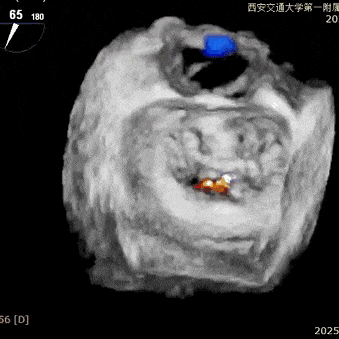

经专家团队评估后决定于2区正中位置先植入一把XTR,植入后评估反流改善情况,如仍有反流,可调整第一把夹子放置于2区偏内,再于第一把夹子外侧植入第二枚夹子,改善对合和反流。

术中在超声引导下完成房间隔穿刺,将第一枚XTR在左房内完成终定位,2偏3区完成植入,夹合效果良好,即刻超声显示轻微反流,完成夹子释放,手术效果良好,手术圆满结束,患者术后6小时即实现床旁活动。